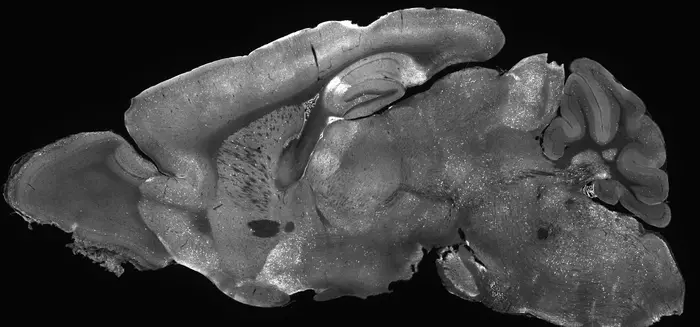

Mouse brain image glowing with experimental gene supplementation therapy highlighting how AAV delivers treatment across the entire brain. Credit: Allen Institute/Andrew Clark